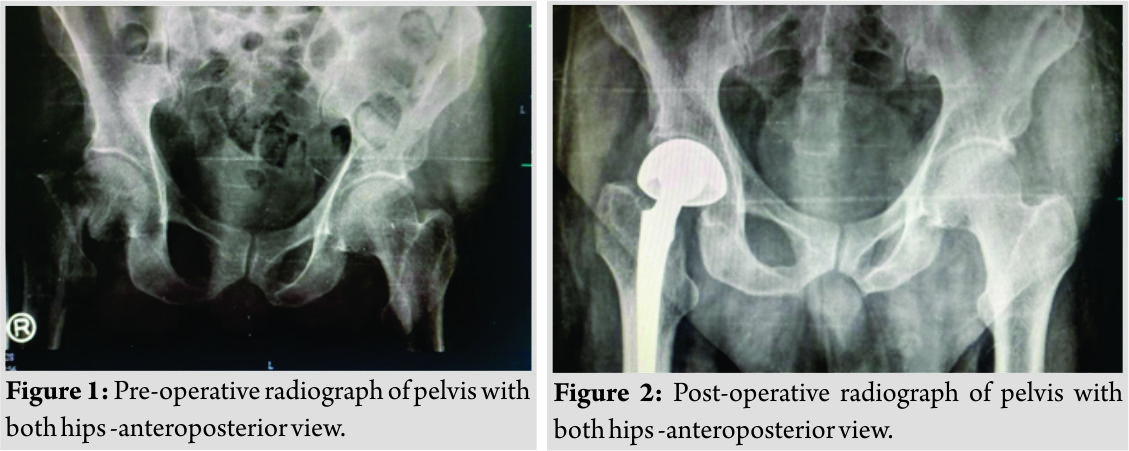

Case Report: We report a case of 72-year-old male presenting with the right hip pain for 2 days and inability to bear weight on the right lower limb following history of domestic fall 2 days back. Radiograph of pelvis with both hips anteroposterior view and lateral view of the right hip showed right fracture neck of femur. The patient was scheduled for surgery next day but was deemed unfit on the ground of electrocardiogram reports showing ventricular arrhythmia. Cardiologist opinion was sought and coronary angiography was done. Coronary angiography revealed triple vessel lumen blockade. The patient underwent CABG 2 weeks after admission. We did cement bipolar hemiarthroplasty for the right fracture neck of femur 1 week later. The patient was mobilized on day 2 using walker. Follow-up radiograph showed acceptable prosthesis position.

A 72-year-old male patient presented to our emergency department with the history of domestic fall, right hip pain, and inability to bear weight on the right lower limb. The patient was a known case of ischemic heart disease with unstable angina, Type 2 diabetes mellitus, hypothyroidism, and end-stage renal disease. Initial clinical evaluation revealed tenderness at the right hip, unable to do active straight leg raise test on the right side, and restricted range of movements of the right hip in all planes. There was no external wound, sinus or discharge from any skin sites. Plain radiograph of pelvis with both hips and the right hip lateral view showed fracture neck of femur, AO type 31 B3, in the transcervical region (Fig.1). Laboratory tests showed hemoglobin -14.9g/dl, total leukocyte count – 15460/cumm, neutrophils – 65%, lymphocytes – 30%, blood urea – 73, serum creatinine – 2.3, and fasting blood glucose level – 220mg/dl. According to K-DOQI criterion, our patient had glomerular filtration rate<30ml/min/1.73m2, our patient was identified as having end-stage renal disease [3].However,for unstable angina, there are no laid down guidelines. The patient was scheduled for cemented bipolar hemiarthroplasty next day. However, the patient suffered chest pain and investigations revealed myocardial infarction. Hence, surgery was postponed. Angiography revealed lumen blockade in major vessels. The left anterior descending showed 85% stenosis, middle and distal right coronary artery 95% stenosis. In view of triple vessel disease, early CABG was planned. Due to pre-operative deranged renal function parameters and urinary tract infection, CABG was further postponed. Following normalization of renal parameters and treatment of urinary tract infection, the patient underwent CABG, 3 weeks after trauma. Postoperatively, the patient was shifted to cardiac care unit for monitoring. 1 week following CABG, the patient underwent cemented bipolar hemiarthroplasty for fracture neck of femur (Fig.2). Surgery was performed under general anesthesia. Preoperatively, blood was arranged to replenish excessive blood loss and bipolar electrocautery was used intraoperatively to achieve hemostasis. As the bone was grossly osteoporotic, cemented hemiarthroplasty was done. The procedure was uneventful. The patient was mobilized on day 2 with walker assistance. Sutures were removed on day 14 and ambulation with stick was started after 3 months. Initial follow-up at 2 weeks, 3 months, and 6 months post-operative and plain radiography of the right hip in anteroposterior and lateral view showed well-fixed prosthesis in acceptable central position without any evidence of loosening or subsidence. We advised our patient not to squat or sit crossed leg to prevent implant dislocation. The patient was community ambulator following surgery. He died due to cardiorespiratory arrest, 2 years after surgery.